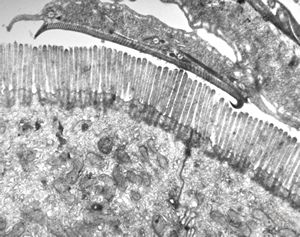

F,52y. | spirochetosis - colon